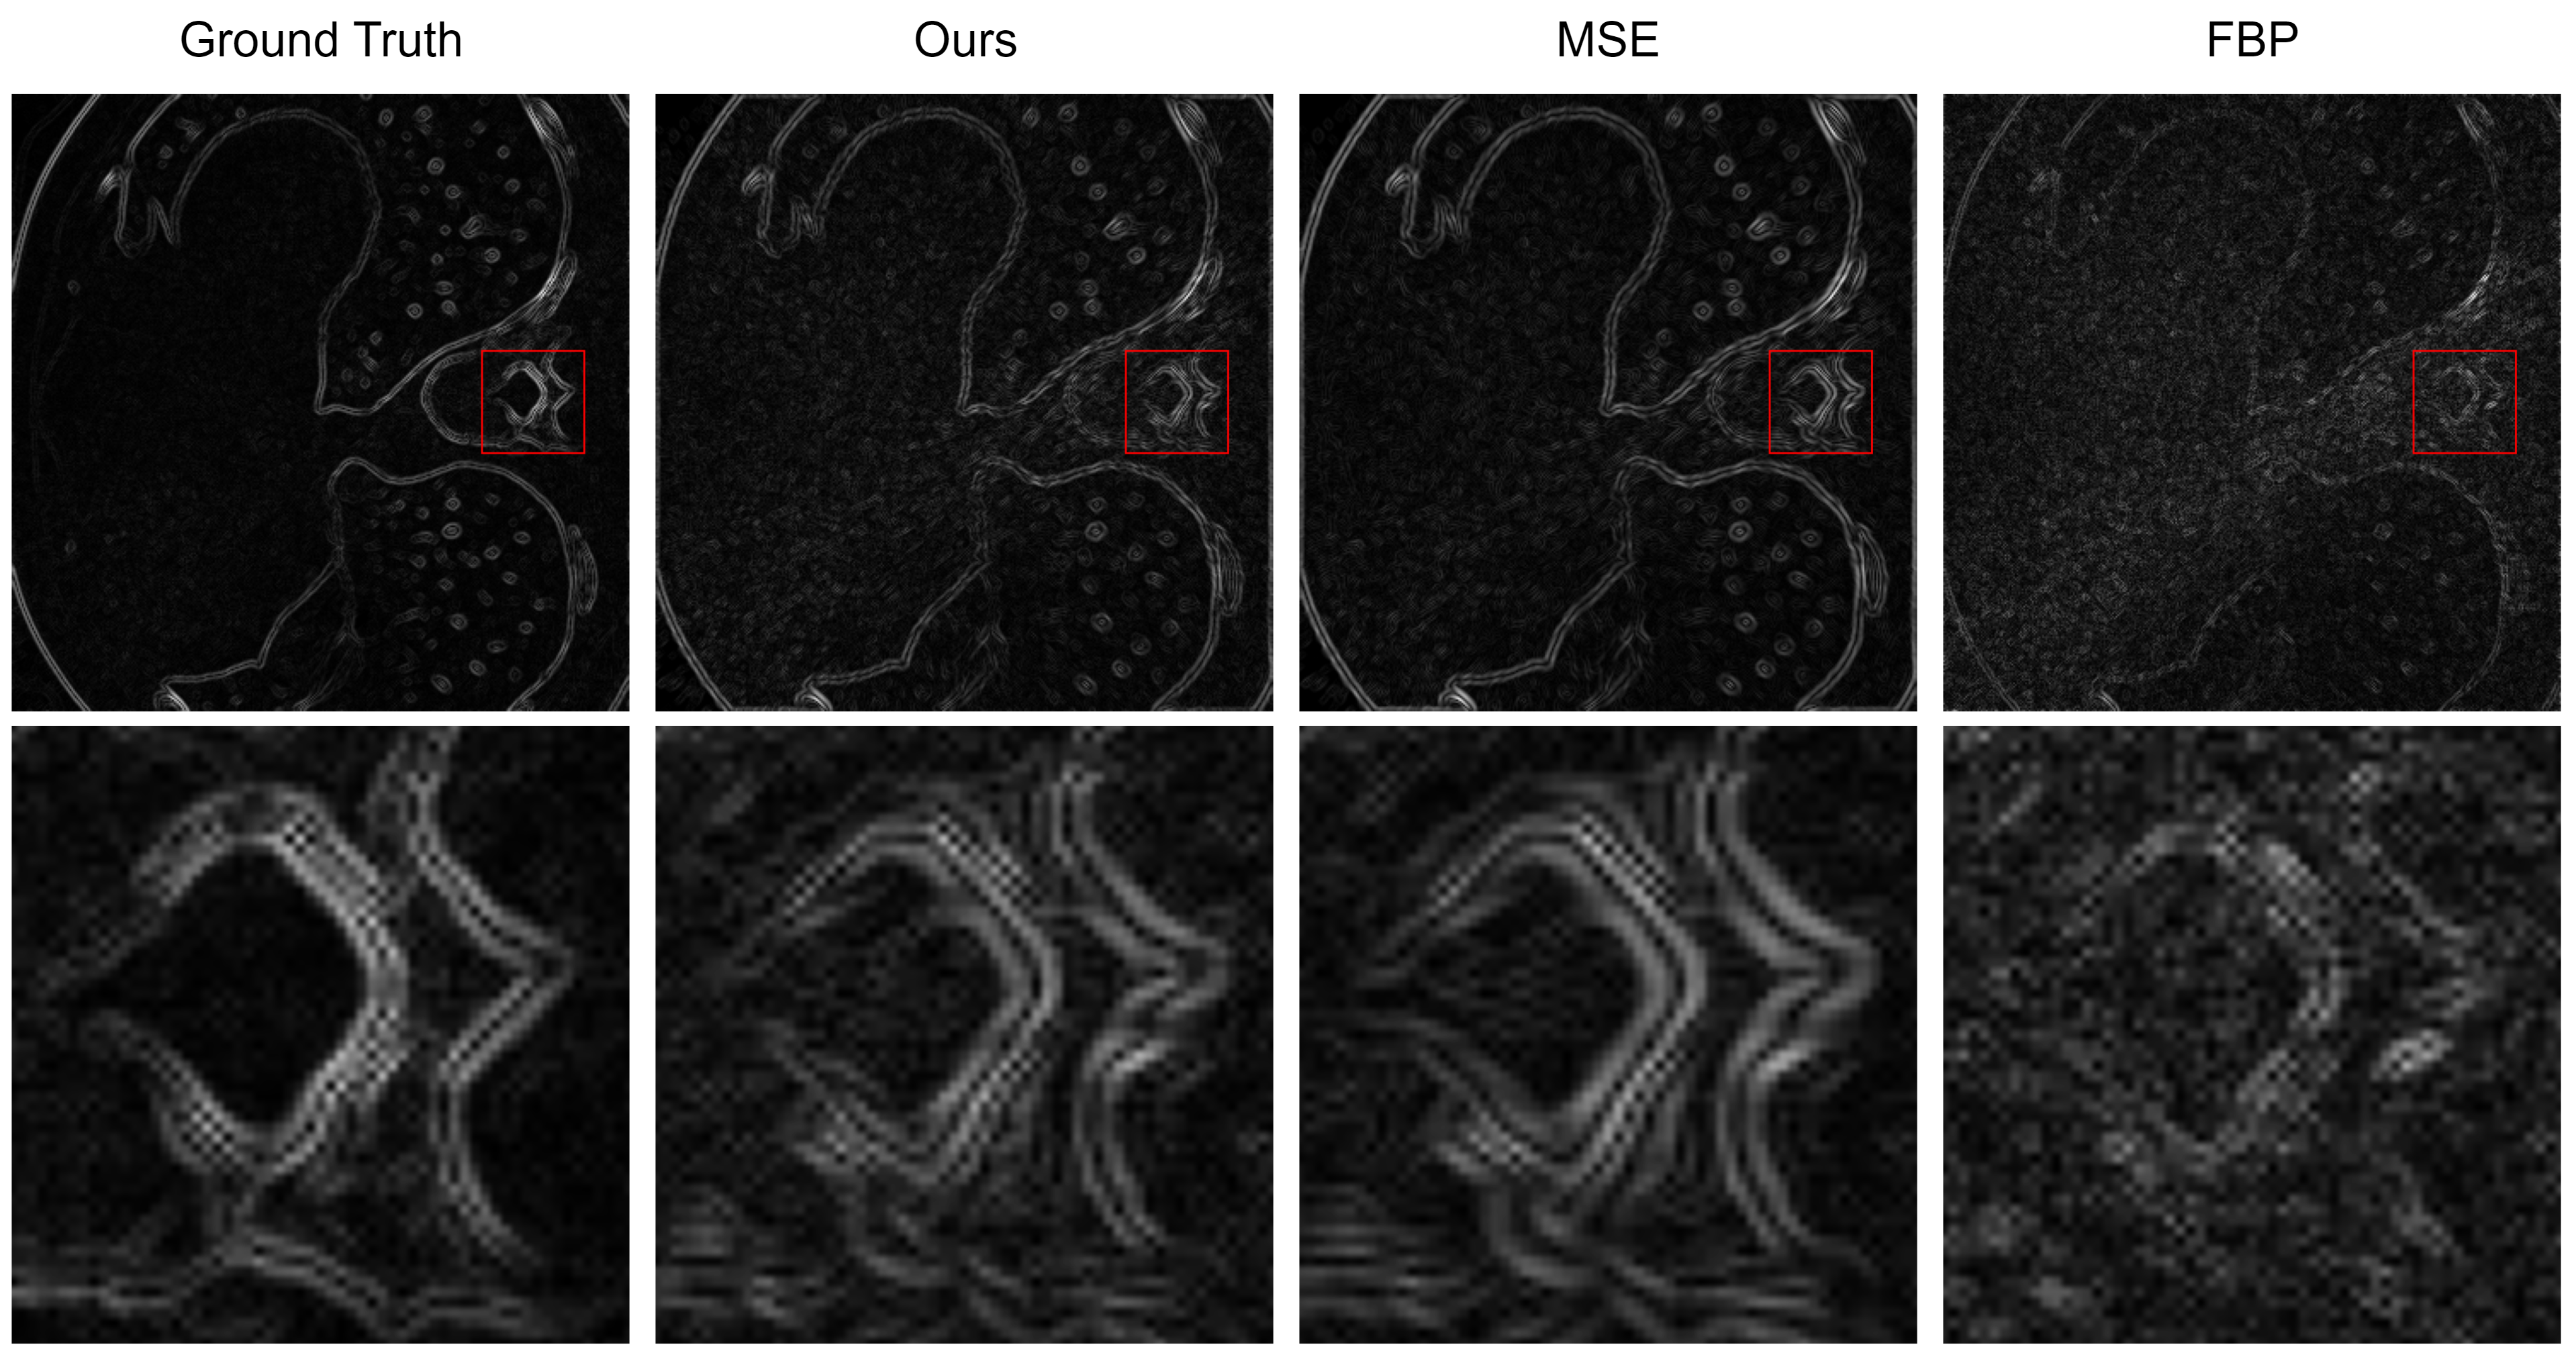

Figure 2 provides a detailed visual comparison of CT image reconstructions utilizing traditional methods such as FBP, MSE optimization, and our proposed method employing a composite loss function. The effectiveness of the reconstruction techniques is particularly observed in high-contrast regions, which are crucial for identifying and evaluating clinical features. Our method’s reconstruction, distinctly visible in the red boxed insets, reveals a significant enhancement in the preservation of geometrical structures, especially evident in the vertebral architecture within the chest CT scans.

Figure 2: Comparative analysis of reconstruction results: When compared to MSE, our composite loss function demonstrates superior detail retention and image sharpness. In comparison to the traditional FBP method, our approach excels in high-frequency noise suppression and provides clearer structural definition.

Delving deeper into the qualitative analysis, Figure 3 employs the Laplace map, a second-order gradient representation that accentuates regions of rapid intensity change, often associated with edges and other structural details in medical images. The bright bands in the Laplace map correlate with edges in the image; narrower bands represent sharper edges. The reconstruction of our model demonstrates narrow bands within the zoomed regions, indicating a preservation of edge sharpness.

Figure 3: Comparison of reconstruction in Laplace map: In contrast to supervised training using MSE, our approach demonstrates superior edge sharpness. When compared to the conventional FBP method, our approach showcases a more distinct edge structure and reduced high-frequency noise.